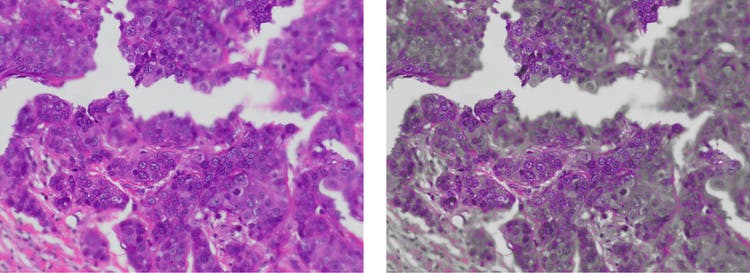

Olympus Smart Image Averaging (OSIA): 빠른 프레임 레이트를 유지하면서 노이즈를 감소시키고 아티팩트를 없앱니다.

디지털 현미경 카메라의 이미지 평균화를 통한 노이즈 감소

OSIA 미사용(왼쪽)과 OSIA 사용(오른쪽)의 비교